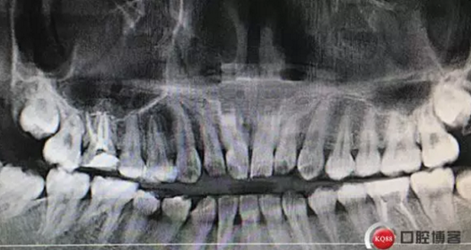

治療計(jì)劃:36局麻下拔除碎片,攝片檢查余留牙體組織。16完善根管治療,擇期修復(fù)。

這是折線的位置,右是拔出的牙齒碎片。很明顯折裂波及遠(yuǎn)中頰根。

先去了充填物,去腐,牙齦電切。根折根上段少量,沒有破壞根管結(jié)構(gòu)。選擇保留患牙。